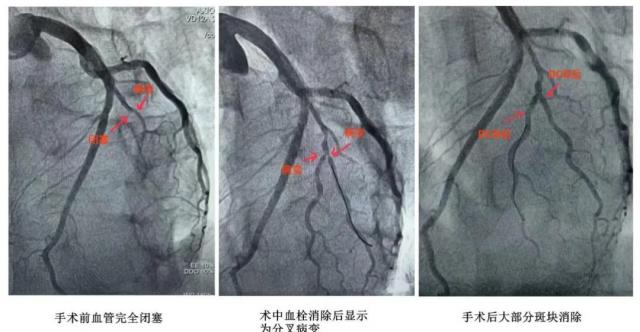

赵军礼主任医师团队迅速响应,开通绿色通道,首次对病人进行急诊冠状动脉造影。造影显示,粗大的对角支主支阻是这种疾病的罪魁祸首。大夫立刻以最快的速度,利用球囊扩张开通闭塞血管。,仅用时 30 一分钟后,病人的胸痛迅速得到缓解,摆脱了死亡的危险。

随后,医生团队立即采取了下一种治疗方法。血管开通后,造影显示,粗对角分支的血液供应范围较大,主分支的阻塞部位与其分支部位呈现真正的分叉病变,分叉张口均为 90% 严重狭窄,病变复杂,并伴有急性血栓病变。如果按照传统方法植入支架,支撑系统可能会堵塞,手术风险和难度会增加,手术时间也会大大延长。

经过全面分析,团队严格遵循操作规程,迅速去除斑点后,用药物球囊将治疗药物送到病变部位。手术后,再次造影显示血管没有明显的血栓形成,没有明显的隔断,血流恢复正常,生命体征稳定,手术成功。术后沈先生病情稳定,目前已顺利出院。